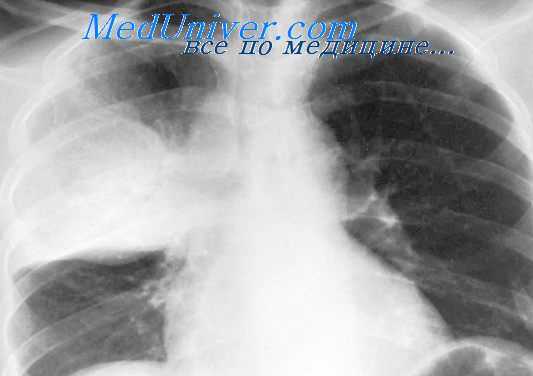

Туберкулез внутригрудных лимфоузлов

При туберкулезе ВГЛУ симптоматика обусловлена сдавлением крупных бронхов и органов средостения увеличенными лимфоузлами. Для данной формы характерны сухой кашель (коклюшеподобный, битональный), увеличение шейных и подмышечных узлов. У детей раннего возраста нередко возникает затрудненный выдох - экспираторный стридор. Температура субфебрильная, могут иметь место фебрильные «свечки».

Признаки туберкулезной интоксикации включают отсутствие аппетита, снижение массы тела, утомляемость, бледность кожи, темные круги под глазами. На венозный застой в грудной полости может указывать расширение венозной сети на коже грудной клетки. Данная форма нередко осложняется туберкулезом бронхов, сегментарными или долевыми ателектазами легких, хронической пневмонией, экссудативным плевритом. При прорыве казеозных масс из лимфоузлов через стенку бронхов могут формироваться легочные очаги туберкулеза.